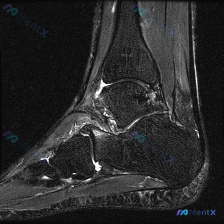

看到这个膝关节读片的病例,整理了完整信息和分析思路分享给大家。 病例基本信息 核心问题:临床怀疑膝关节存在软骨异常,提供单张膝关节矢状位MRI,请分析图像中的明显发现。 影像基础信息 这是一张清晰度良好的膝关节矢状位PD/T2加权MRI,左侧为前(髌骨侧),右侧为后,上方为股骨远端,下方为胫骨近端,...

看到这张膝关节MRI读片的需求,问题是观察到「软骨异常」,我整理了一下完整的病例资料和分析思路,和大家分享讨论。 一、影像基本信息 这是一张膝关节矢状位T1加权MRI影像,图像对比度尚可,解剖结构清晰,无明显运动伪影,层面接近膝关节中间矢状面,完整显示股骨远端、髌骨、膝关节间隙及胫骨近端结构。 二、...

看到这个有意思的病例,整理一下完整分析思路分享给大家。 病例影像基本信息 这是一张膝关节矢状位T1加权MRI图像,扫描范围覆盖髌股关节及部分胫股关节,图像对比度良好,可以清晰分辨解剖结构。 我们先按系统读片流程一步步来: 1. 骨骼与对线:股骨远端、胫骨近端、髌骨骨皮质连续,没有明显骨折线;骨髓信号...